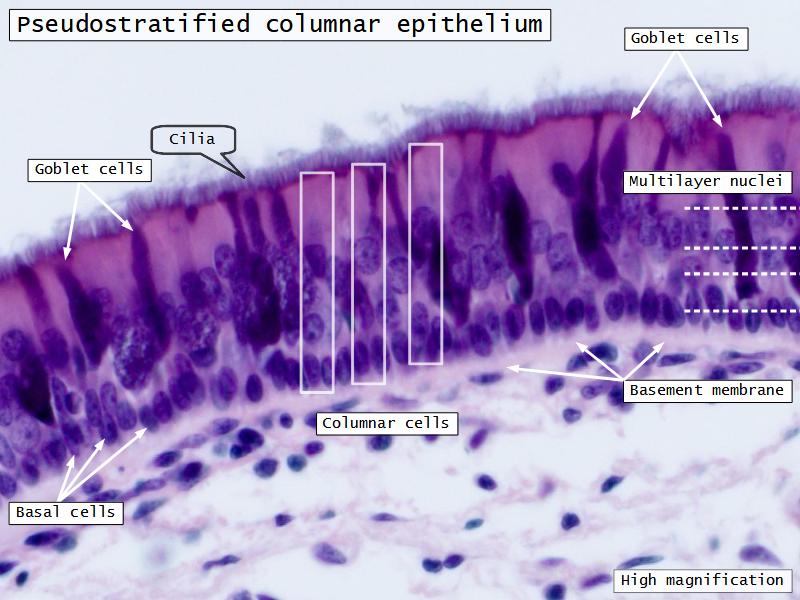

Respiratory epithelium

- Pseudostratified

- Ciliated

- Columnar

- Epithelium with

- 4 Cells

- Ciliated columnar cells

- Non-ciliated columnar cells

- Goblet cells

- Basal cells